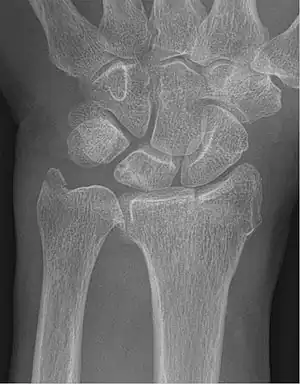

| Fracture of the radial styloid process with the fracture line extending into the intraarticular surface | |

| X-ray of a displaced intra-articular distal radius fracture in an external fixator. The articular surface is widely displaced and irregular. This is a Chauffeur's fracture. Frykman class 3. | |